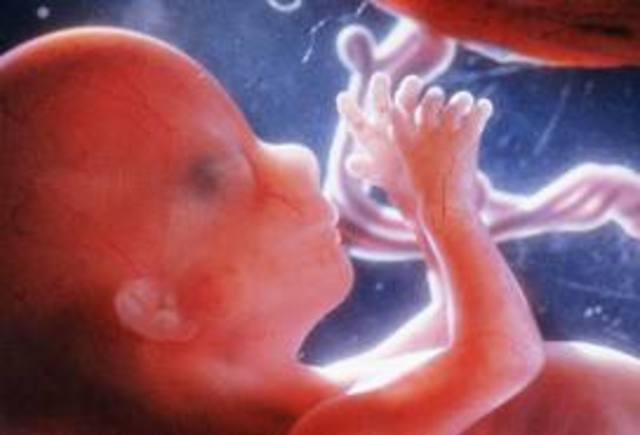

• week 21

week 21

Length is now measured crown to heel.

The fetus has grown to 10.5 inches (27 cm) - 12.7 ounces (360 grams).

It is now gaining weight steadily, with fat being added to the body.

Bone marrow has started making blood cells.

Their small intestine is starting to absorb sugars.